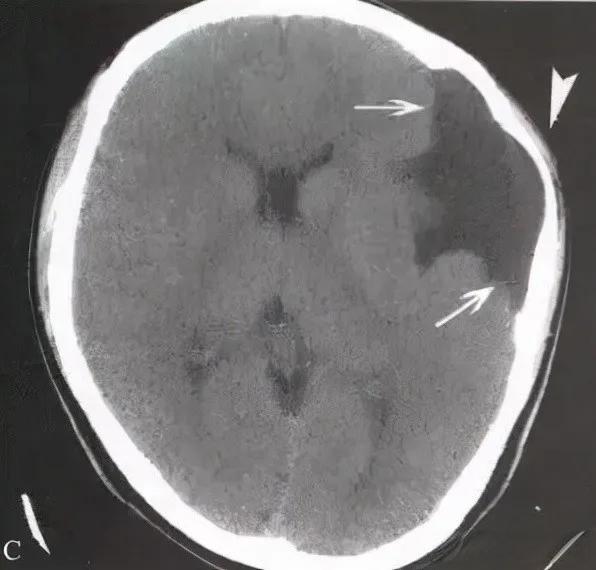

脑穿通畸形又称脑穿通性囊肿,CT扫描可显示一个或多个与脑脊液密度相同的低密度区,与轻度至中度扩大的脑室和蛛网膜下隙相通。病变多位于额叶后部、顶叶前部,同侧侧脑室常呈不对称扩大。